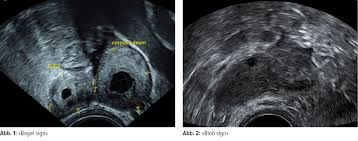

Wann bemerkt man eine Eileiterschwangerschaft. Ultraschall ermöglicht es den eingenisteten Embryo zu lokalisieren Gerade zu Beginn lässt sich eine Eileiterschwangerschaft von einer herkömmlichen Schwangerschaft kaum unterscheiden. Wann bemerkt man eine Eileiterschwangerschaft. Bei einer Eileiterschwangerschaft Extrauteringravidität nistet sich die Eizelle nicht wie vorgesehen innerhalb der Gebärmutter sondern im Eileiter ein. Denn die Symptome einer Extrauteringravidität Schwangerschaft ausserhalb der Gebärmutter sind dieselben wie bei einer normalen Schwangerschaft. Die Schwangerschaft wächst heran was anfangs unbemerkt erfolgt. Antwort von Sille20 am 27042012 1041 Uhr. Das passiert aber nur sehr selten. Wie merkt man eine Eileiterschwangerschaft.